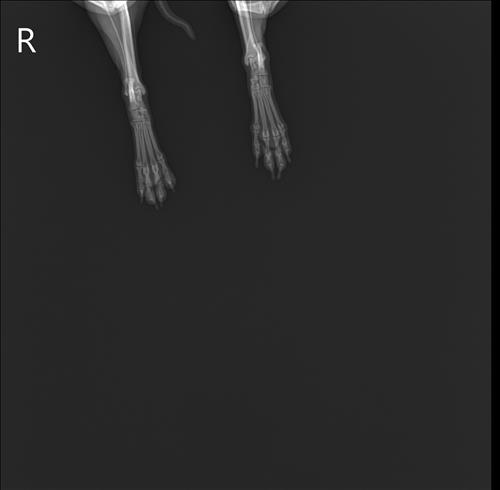

2016년생 10세 8kg 비숑입니다

오른쪽 뒷다리를 서있을째 떨다가 이젠 깽깽이발을 하길래 근처 동물병원을 갔더니 십자인대가 손상됐다고 했어요 파열이 아니라 체중감량하고 약물 처방 해줬다는데 진통제라 치료의 개념은 아니라고 생각하는데 근본적인 치료는 수술이 맞을까요..?